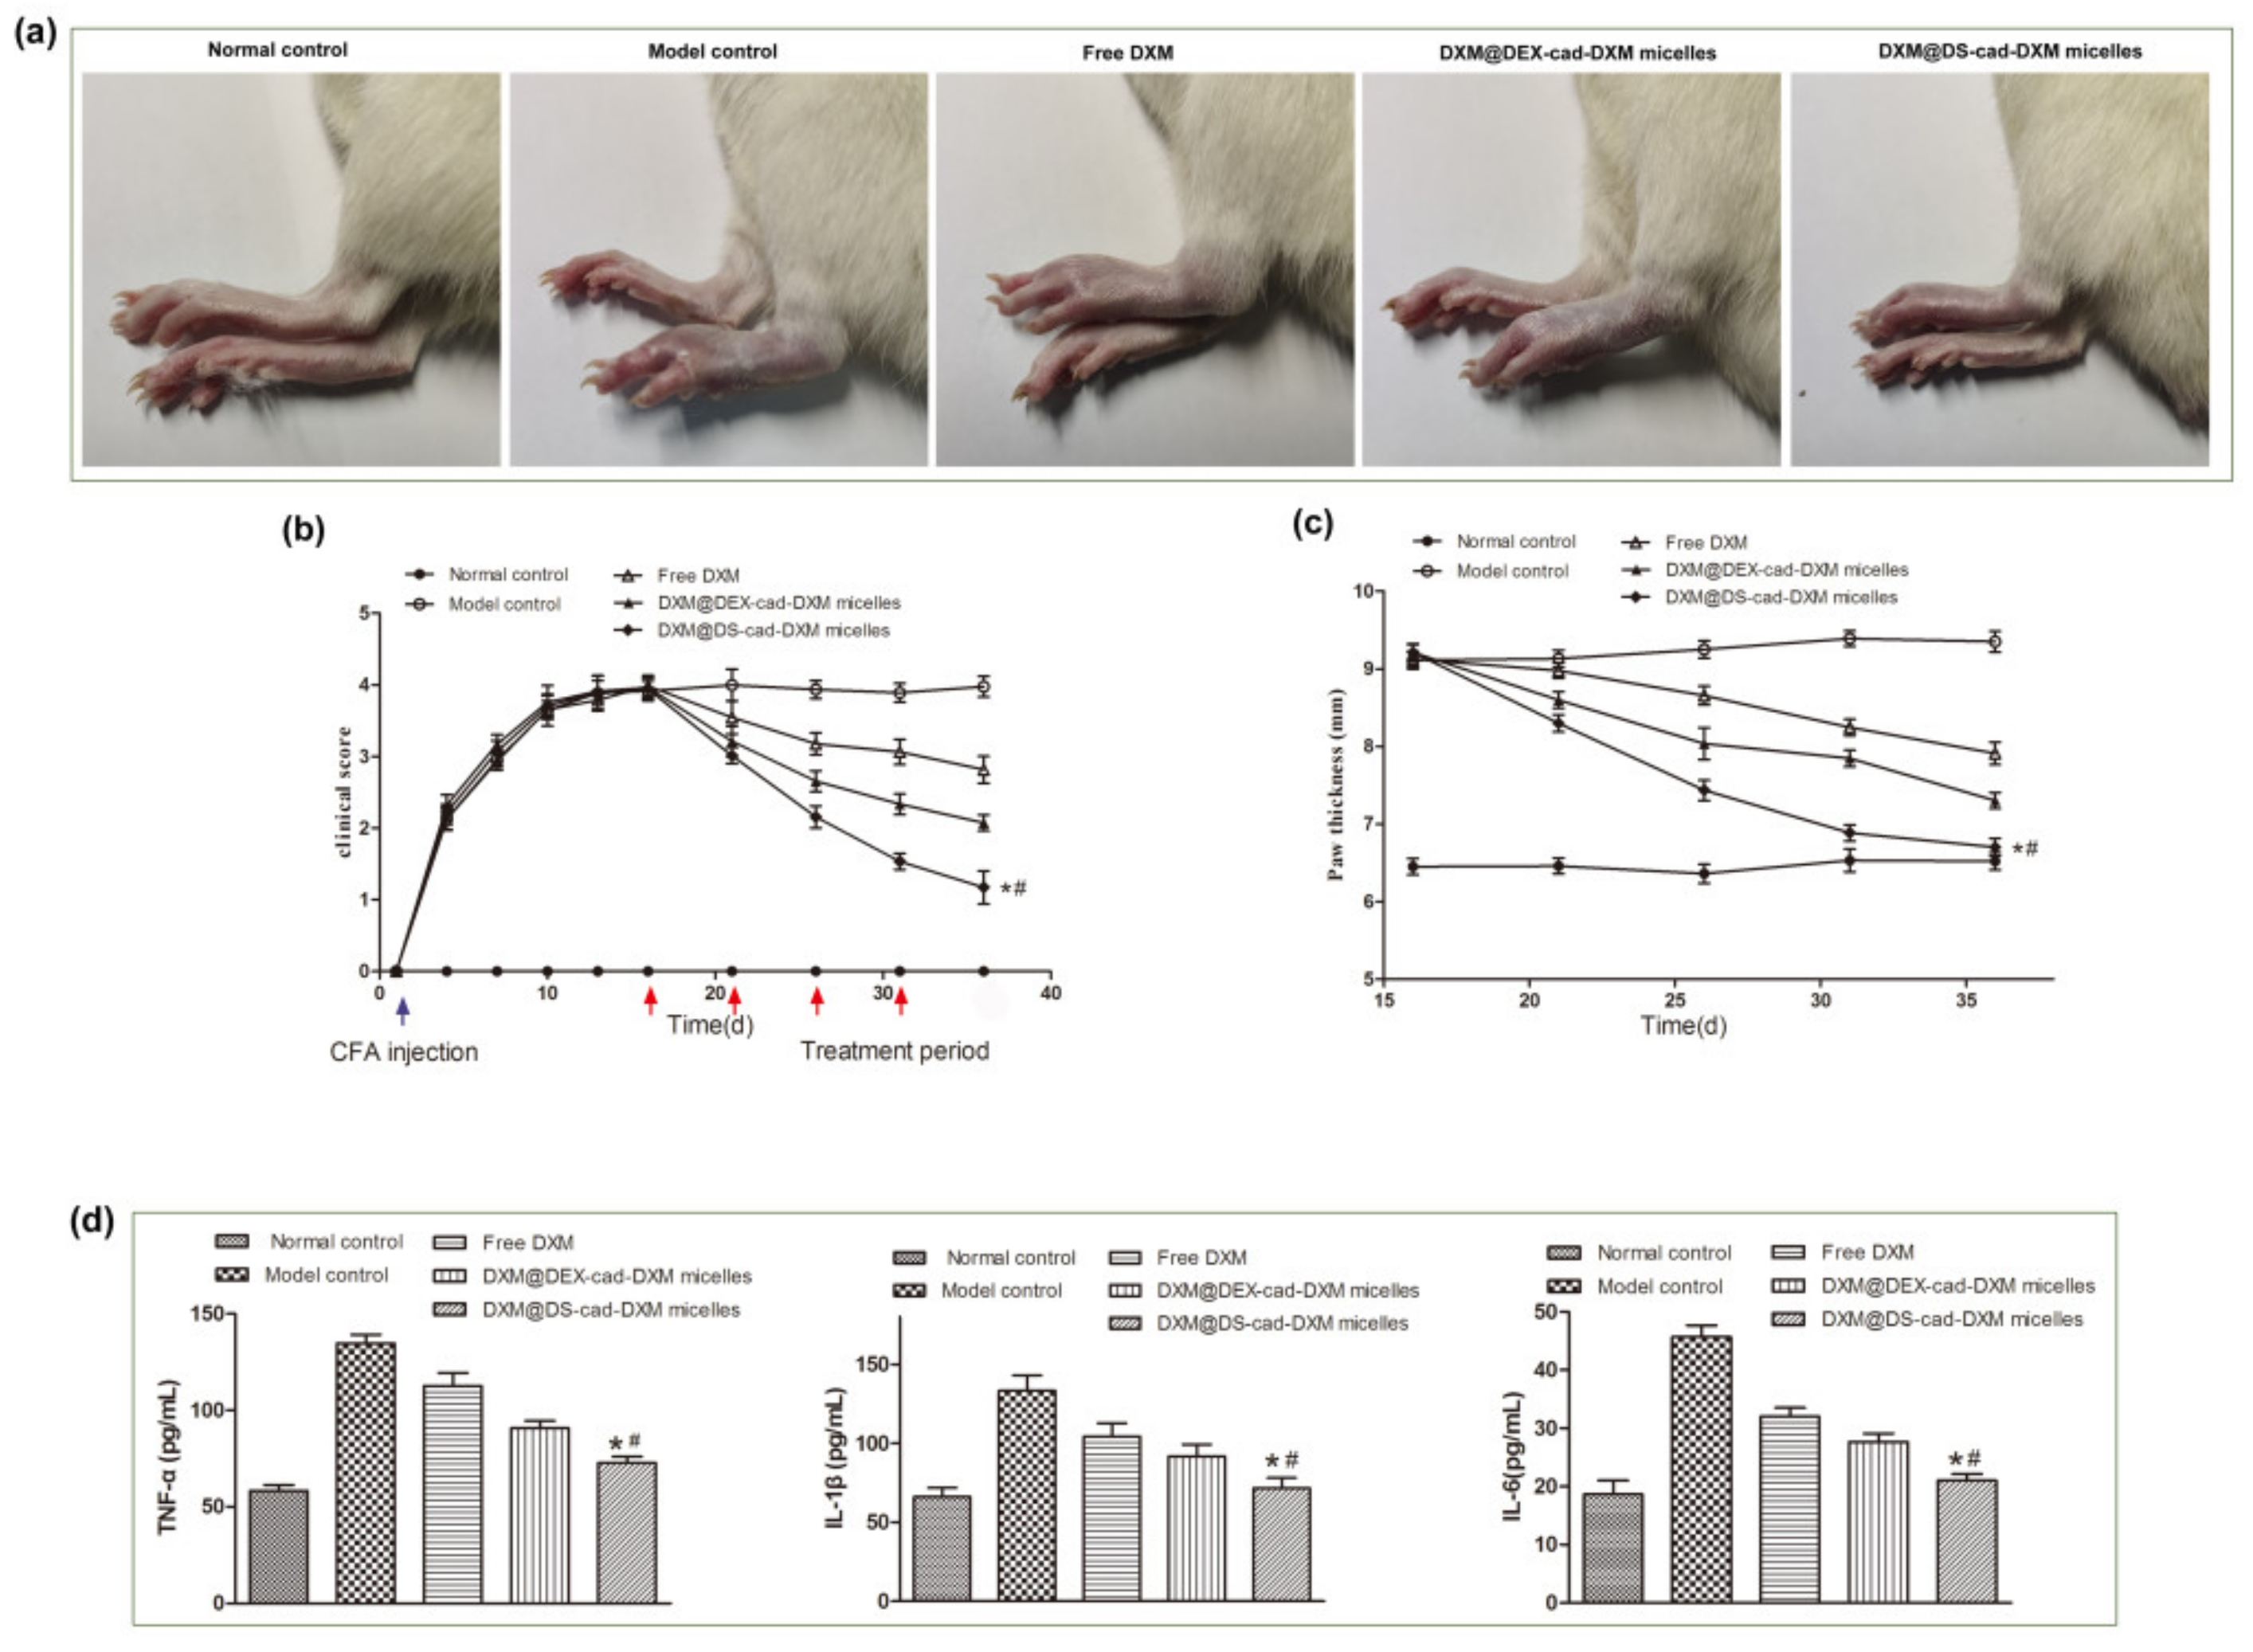

2.6. Therapeutic Efficacy of AIA Models

3.10. In Vivo Therapeutic Efficacy of DXM@DS-cad-DXM